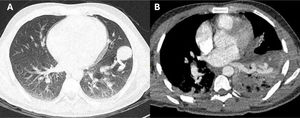

Como parte del estudio para identificar la localización del shunt extracardiaco, se realizó una tomografía pulmonar con presencia de malformación arteriovenosa (MAV) (fig. 4).

Tomografía pulmonar. A) TC de tórax simple, ventana parenquimal. Áreas de componente consolidativo atelectásico bilateral de predominio inferior izquierdo con un área noduliforme de 30mm periférica subpleural basal anteroizquierda adyacente al componente vascular. B) Angiotomografía de tórax. Se destacan estructuras vasculares anómalas a manera de malformación arteriovenosa en región inferoanteroizquierda dependiente de ramas segmentarias de la arteria pulmonar izquierda y eferencia hacia vena pulmonar inferoizquierda.

Fuente: Hospital Nacional Edgardo Rebagliati Martins, Servicio de Imagenología.